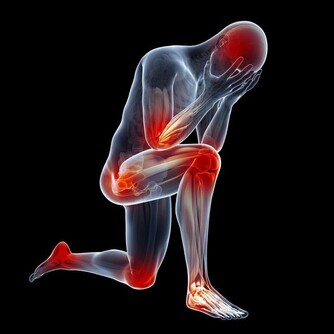

醫學認為,汗皰疹是濕疹的一種,是一種對稱性的、複發性的、多發生在手掌的水皰性疾病。汗皰疹發病有以下特點:

2、水皰為位於表皮深處的小水皰,米粒大小,半球形,略高於皮表,分散或成群發生在手上;

5、一般無瘙癢、疼痛等異常感覺。